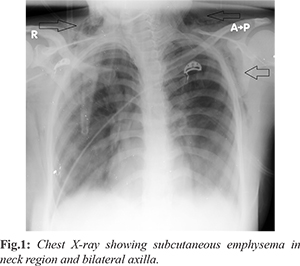

A 20 year old female complaining of cough and dyspnea since five days presented to the Emergency Department (ED) at an urban tertiary care hospital. She also had a complaint of neck pain and swelling since one day. Patient was unmarried, non-smoker and was a known case of bronchial asthma since childhood. She had a history of non-compliance to medications. She was administered nebulised medication one day prior at another health centre facility. On admission her pulse rate was 140/min, respiratory rate: 24/min and blood pressure: 110/70 mmHg. She was saturating at 89% on room air which increased to 98% on 6-7 L/min humidified oxygen by face mask. Chest auscultation revealed extensive bilateral rhonchi. On further examination patient had palpable crepitations in supra-clavicular fossa extending to neck bilaterally. Auscultation on neck revealed rhonchi with crepitations on pressure. Chest X-ray showed normal lung fields with increased lucency along subcutaneous tissue of neck and axilla bilaterally diagnostic of subcutaneous emphysema in neck region and bilateral axilla [Fig.1]. She further underwent high resolution computed tomography chest which revealed significant pneumo-mediastinum and marked emphysematous changes noted in the soft tissues of visualised neck and the upper chest walls [Fig.2-4]. On the basis of the history, examination and radiological findings, a diagnosis of acute exacerbation of bronchial asthma with pneumo-mediastinum and subcutaneous emphysema was made. She was treated with nebulized salbutamol and parenteral hydrocortisone. She was further admitted into the intensive care unit under the pulmonology team where she was kept on oxygen enriched air, bronchodilators, parental antibiotics and steroids, oral oseltamivir and other supportive treatment. Patient gradually improved and finally patient left the hospital against medical advice.